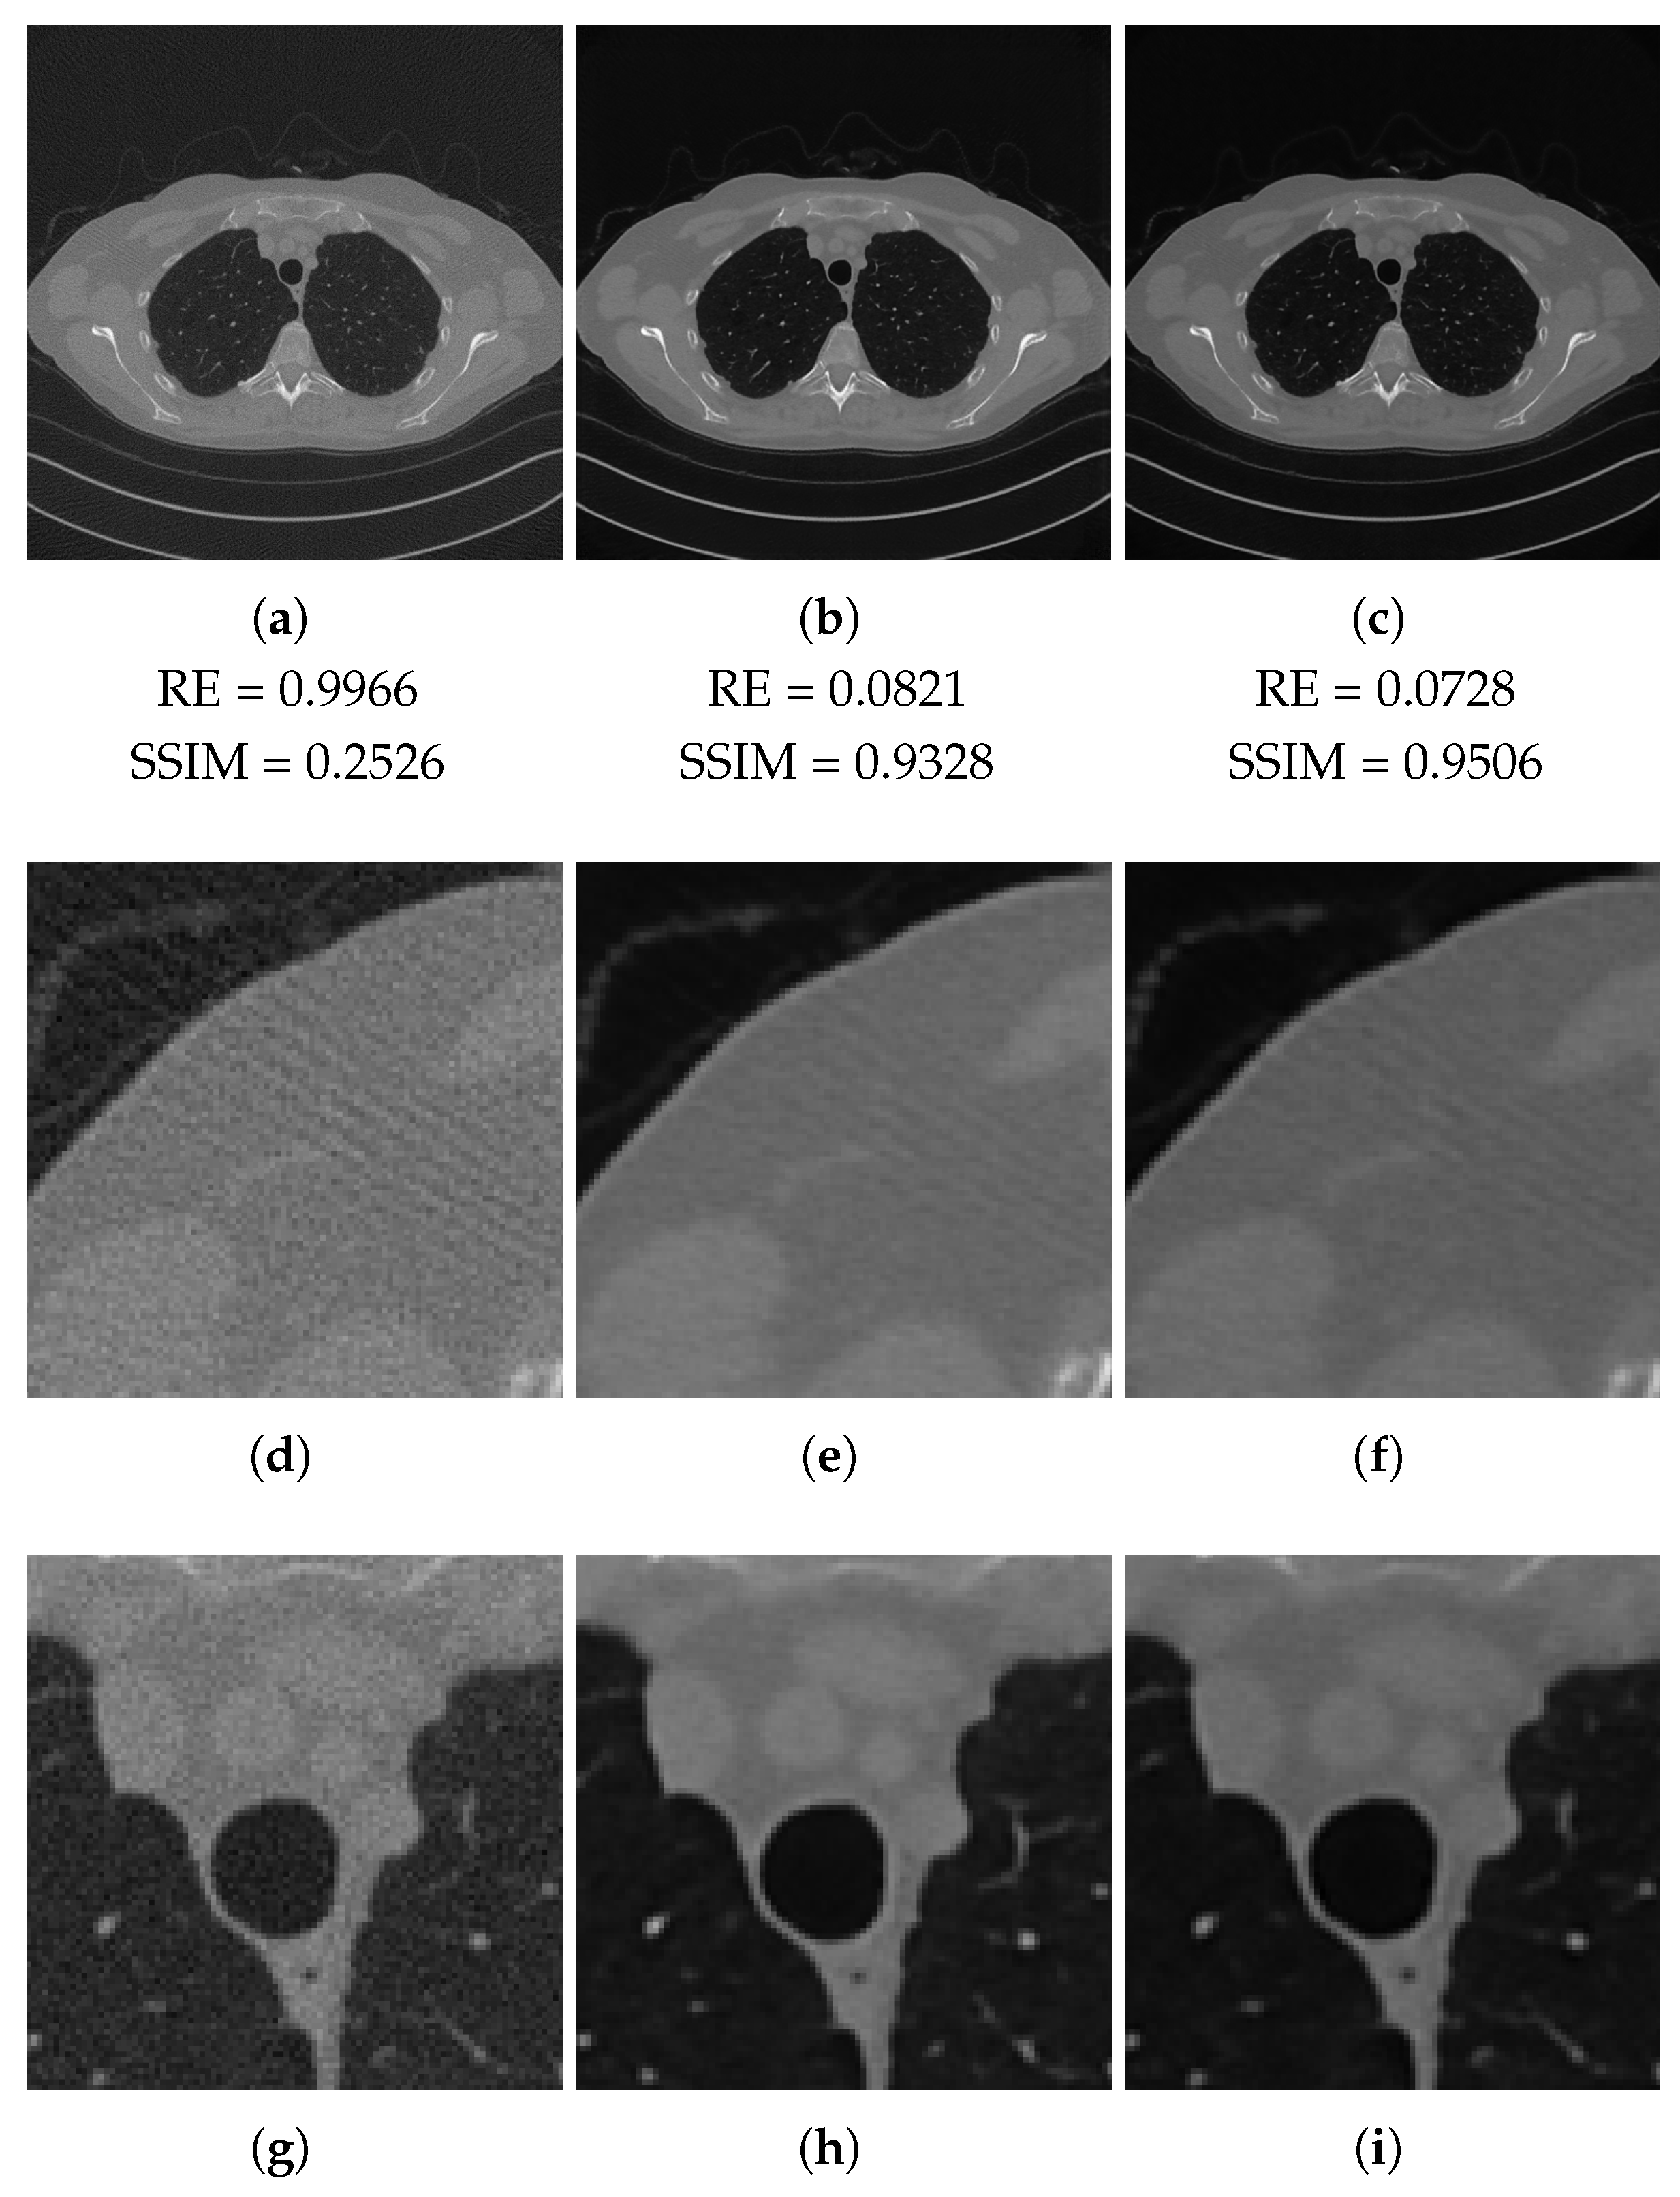

| RE | SSIM | RE | SSIM | RE | SSIM | |

| Full-range | 0.9966 | 0.2526 | 0.0966 | 0.9172 | 0.0896 | 0.9295 |

| Half-range | 0.9932 | 0.2567 | 0.0986 | 0.9212 | 0.1162 | 0.8866 |